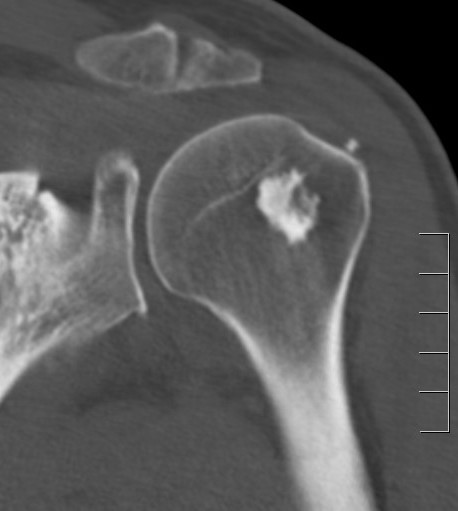

CT

Even cortical texture